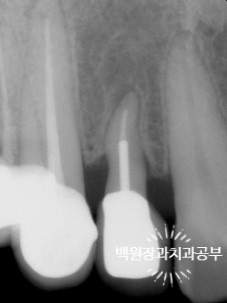

왼쪽이 외과적 정출술을 마친 직후에 찍은 치근단 엑스레이 사진입니다.

오른쪽이 신경치료와 기둥 식립 그리고 크라운을 접착한 뒤의 엑스레이 사진입니다.

기존에 치아가 위치하고 있다가 빠져나온 자리는 이제 치조골로 채워져서 방사선상에서도 구별하기가 어려워졌어요!!